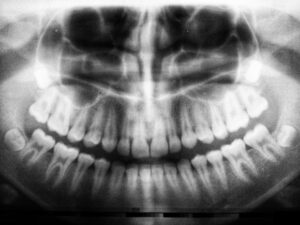

Every treatment begins with a thorough consultation and review of your dental X-rays. We create a custom treatment plan based on your comfort, needs, and whether the teeth are impacted.